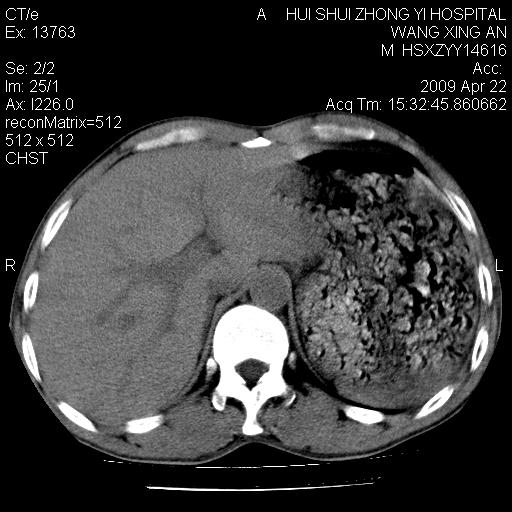

标题: CT19534:患者男、46岁咳嗽、胸痛半月。 [打印本页]

标题: CT19534:患者男、46岁咳嗽、胸痛半月。

1、右下肺中央型肺癌并右肺转移,右肺下叶不张。(肿块围绕右肺下叶支气管生长,致管腔闭塞右肺下叶不张;右肺有结节影)。

2、右侧胸腔积液。

3、右中上肺陈旧性肺结核(右肺见纤维化病灶及点状钙化)。

1、右下肺中央型肺癌并右肺转移,右肺中下叶不张。(右肺有结节影)。胸骨转移

2、右中上肺陈旧性肺结核(因为大多为纤维灶)。

3、右侧胸腔积液。

1)右肺中间段支气管癌并右肺下叶肺不张。2)右肺上叶、两肺下叶背段感染性病变。3)右侧少量胸腔积液。